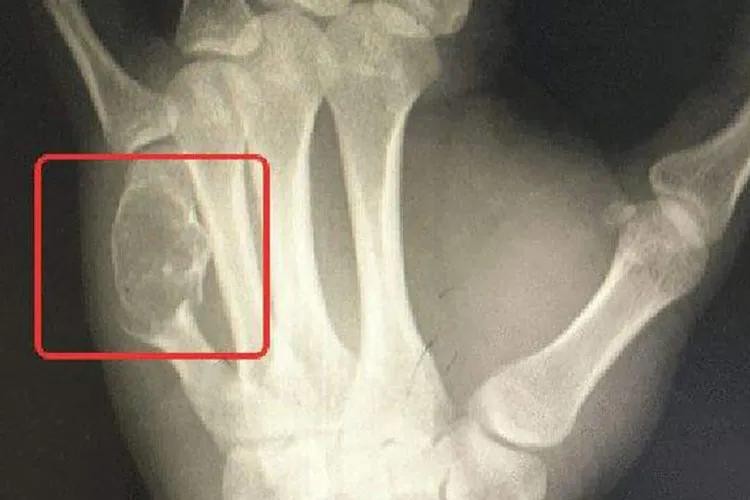

许多骨癌早期并没有典型的症状表现,少数骨癌的早期可出现疼痛症状,开始为间歇性,后来发展为持续性,夜间较明显,晚期疼痛加重。有的病人因疼痛剧烈而抱肤辗转,彻夜不能安眠,疼痛如针刺、刀割、火烧、钻痛,邻近关节有放射性疼痛,影响工作和休息。患者自感肢体疼痛,与肿胀或肿块的部位一致,具有固定性、持续性的特点,甚至服用镇静药无效。一般症状与其他癌症病者一样有食欲减低、体重减轻、发烧等症状。逐渐发展患部之关节与肢体运动受限制,患部皮肤溃烂,肢体远端会有麻木感,甚至发生病理性骨折或变形。

骨癌肿块图

骨癌可通过病史、体格检查及辅助检查来进行诊断。体检检查及X线检查可判断肿瘤部位;CT及MRI检查可显示肿瘤软组织侵犯和髓腔浸润程度;肺CT判断有无肺转移;骨扫描排除骨转移;病理学检查为骨癌确诊依据,通过针吸活检或切开活检进行病理检查,可以明确诊断并进一步确定肿瘤亚型。